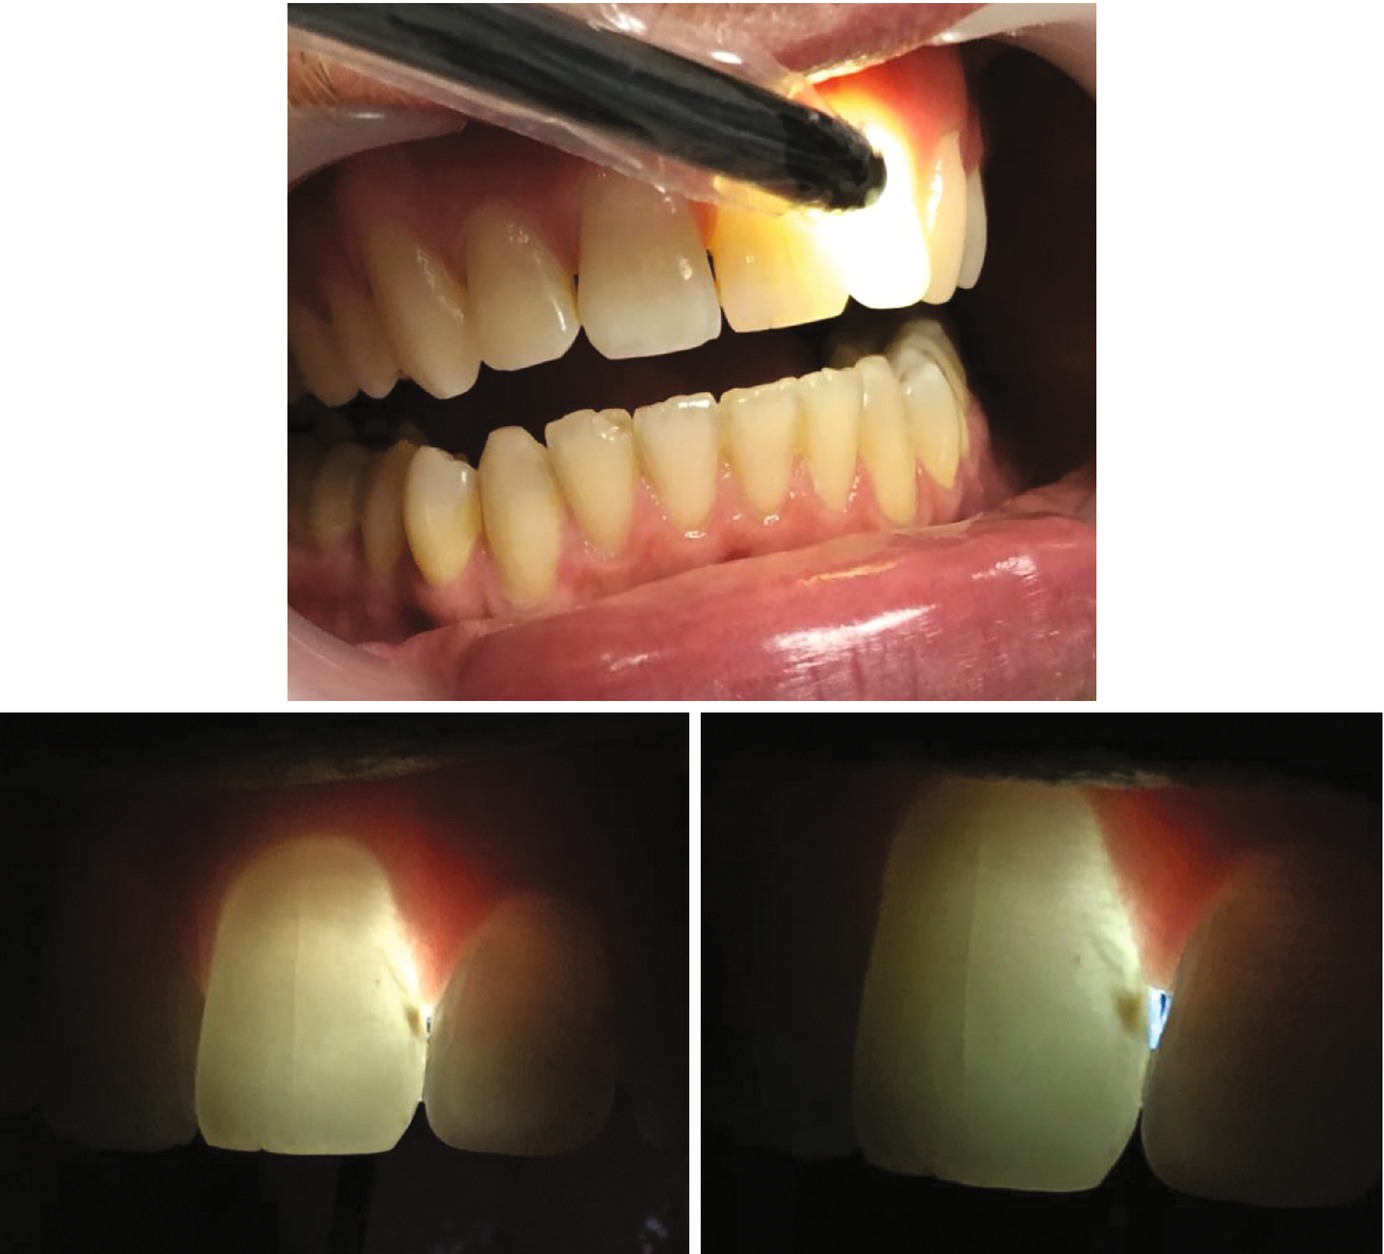

Fiber Optic Light Dental . in this review, techniques for using foti for tooth evaluation are presented along with examples of how foti can be effectively. in this study, we focus on transillumination methods: the experimental results show that the random fiber laser has the best comprehensive quality in dental imaging due to its high spectral. by shining the intense light through tissues (transillumination) the diagnostoset became a diagnostic tool for.

by shining the intense light through tissues (transillumination) the diagnostoset became a diagnostic tool for. in this study, we focus on transillumination methods: the experimental results show that the random fiber laser has the best comprehensive quality in dental imaging due to its high spectral. in this review, techniques for using foti for tooth evaluation are presented along with examples of how foti can be effectively.